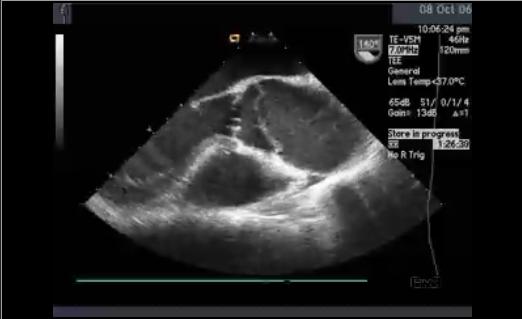

here it is.i am trying to detect the thickness of the heart walls by using either edge probe or the thickness probe. thanks!

Sorry for the obvious question to you but we are not medical folks here ... which edge would the heart wall be? Perhaps you could draw a red line across that edge?

It appears that your above robofile is not configured for this image size otherwise we could have gotten that information from there.

As a guess, we used the thickest edge and have included a robofile that shows that result. Note that your image is embedded in that robofile.

Note that the thickness of that part is 29 pixels (the first number of the results) with the x,y for the measured line as the next 4 numbers.

I think the main issue you were having was to threshold the image prior to measurement. The thickness probe was picking up many different segments since the image fluctuates too much over the span of the wall. Thresholding makes this much easier for that probe to determine a single value.